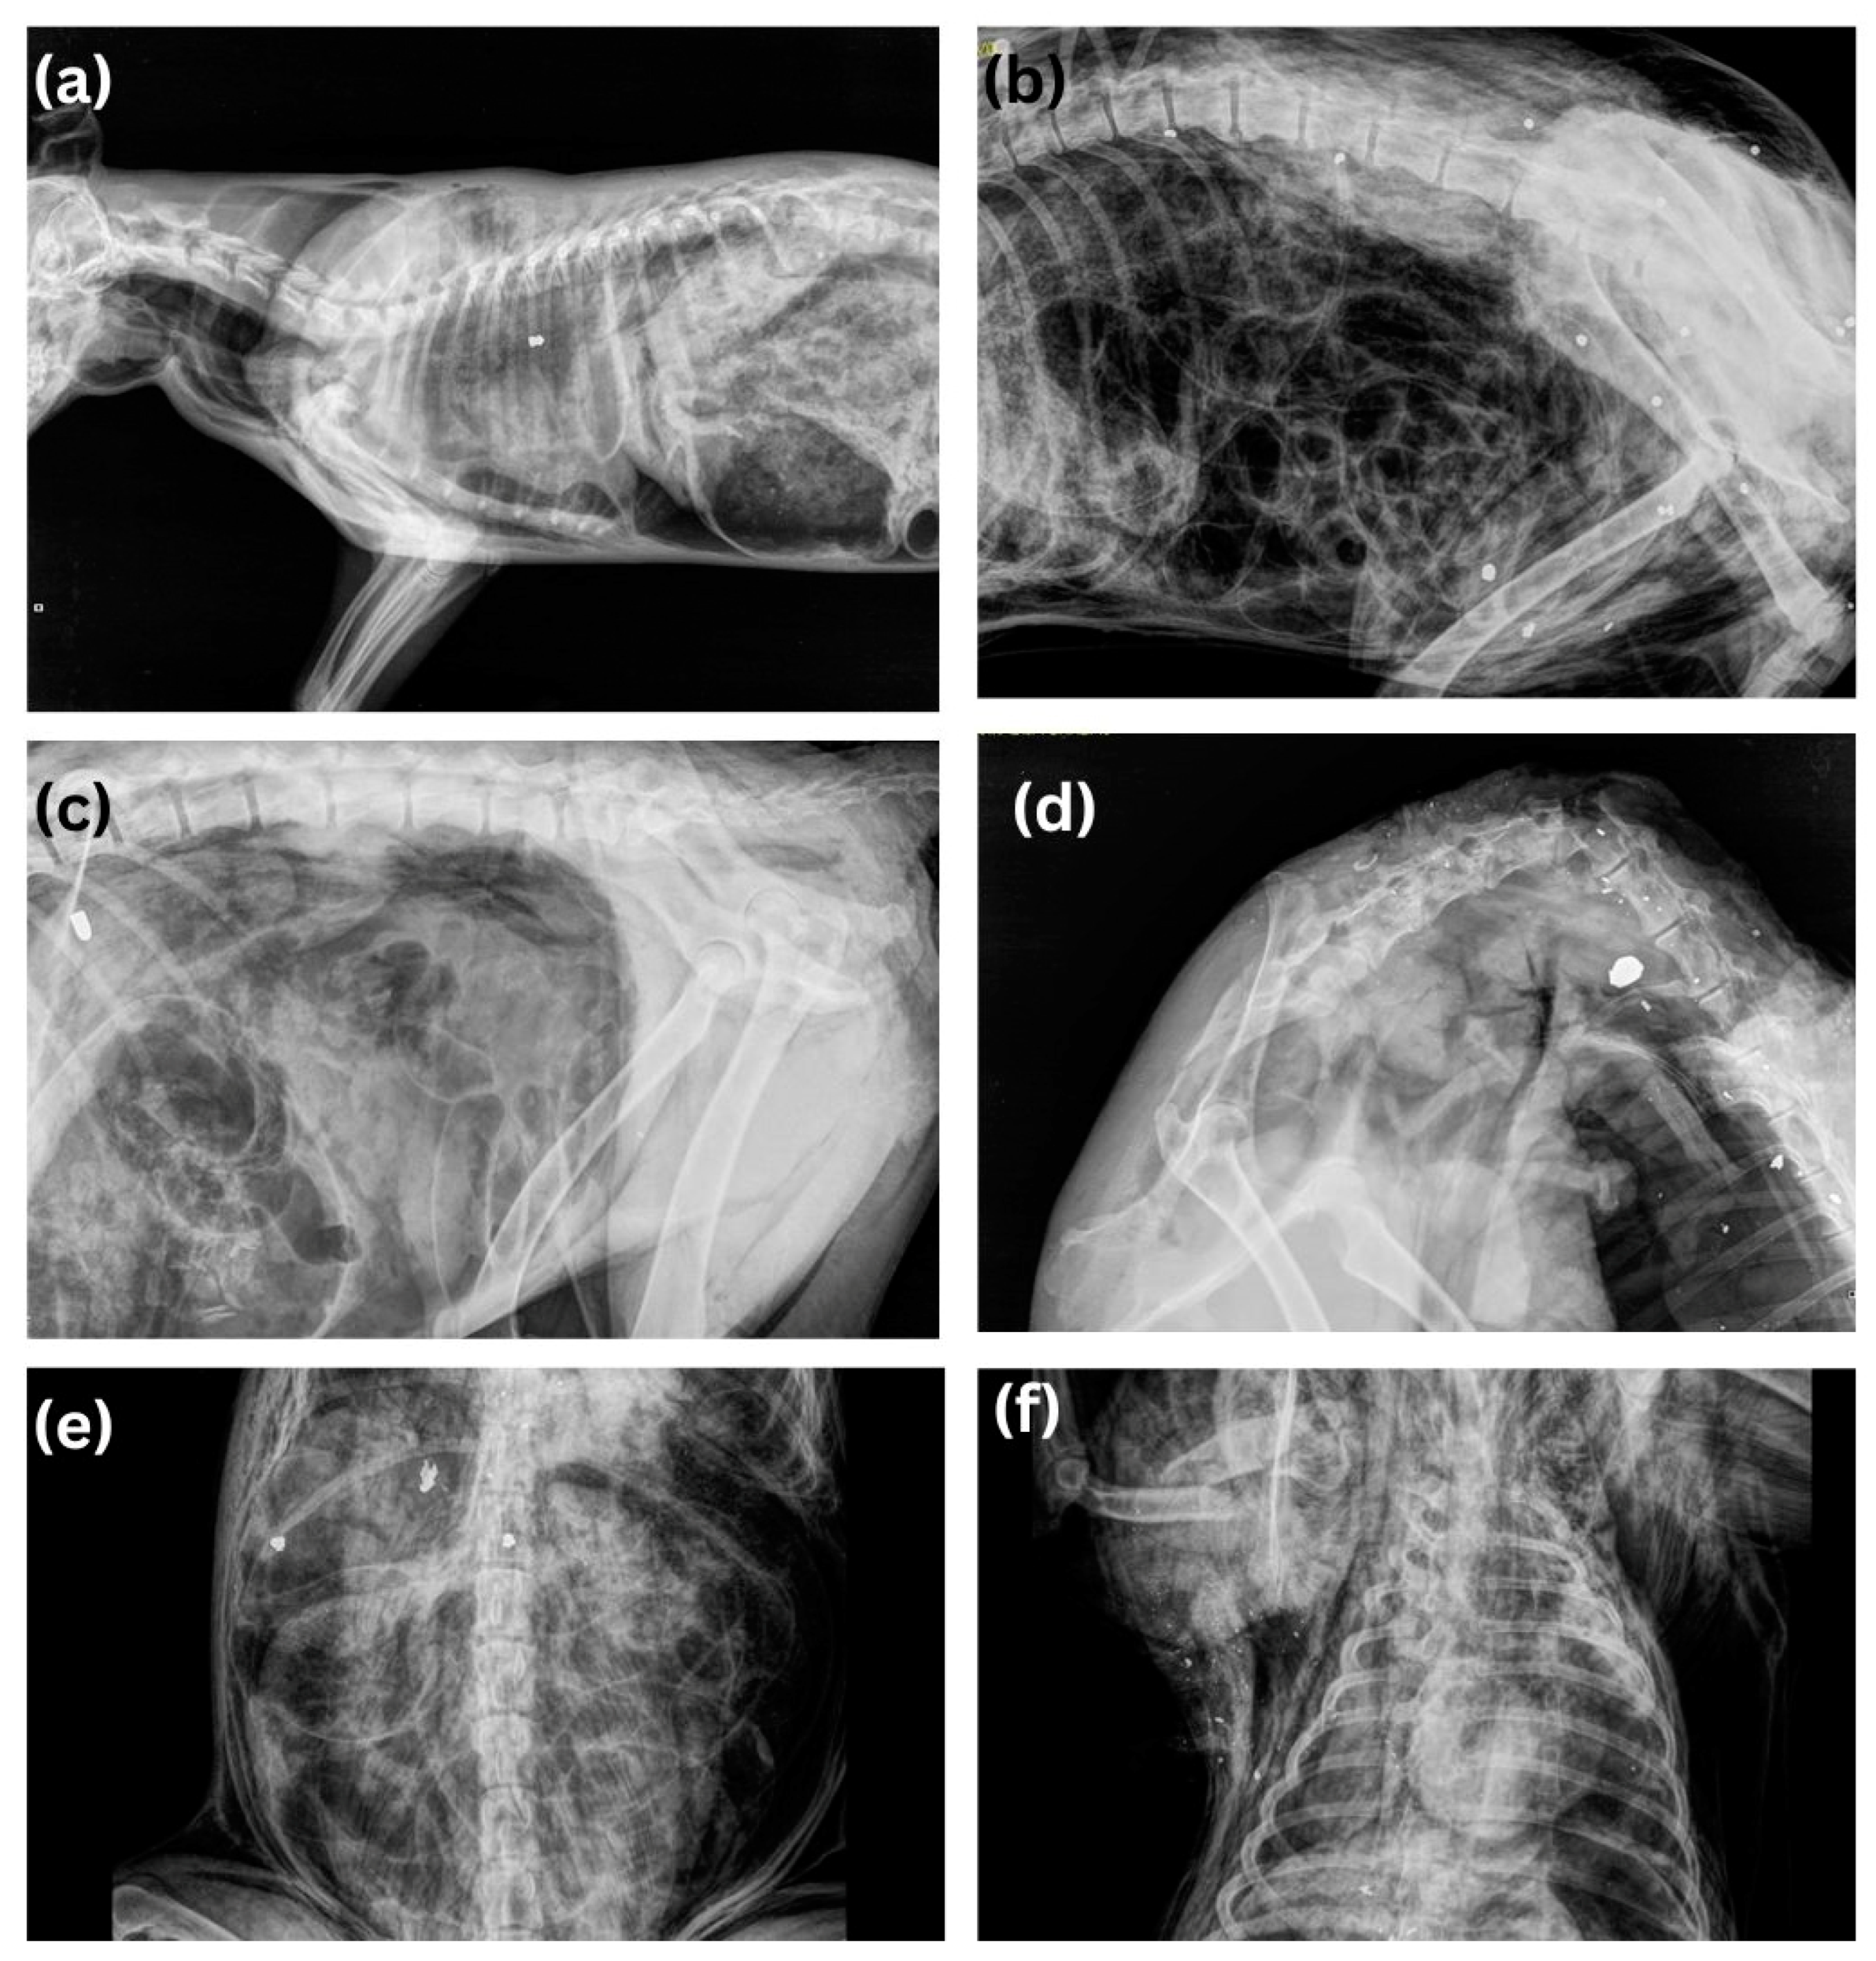

The second most common non-accidental injury and cause of death in dogs was gunshot injuries (n = 41, 12.1%). The most commonly used weapons were guns (46.3%, n = 19), rifles (31.7%, n = 13), air guns (19.5%, n = 8), and crossbows (1 case), respectively. The most affected body regions were the head, fore-limbs and thorax (Figure 4a), and in a case with a crossbow, the massive destruction of internal organs (Figure 4b). Massive hemorrhages due to organ rupture, blood vessel injuries and rib fractures were present in most cases. In all cases except one (infection), the mechanism of dead was hypovolemic shock due to massive bleeding.

Gunshot injuries were the second most common cause of the death in dogs and in cats, after poisoning and blunt force trauma. In rural areas, rifles or shotguns were most commonly used, but in urban areas it was guns that were more common. Calibers such as 0.22 LR (Long Rifle)-caliber weapons are also present and popular in Serbia. This caliber is known for its accuracy, low recoil, and low cost of ammunition, making it ideal for recreational shooting, shooter training, and pest control. These 0.22 LR-caliber weapons include various types of rifles and pistols and are widely available in Serbia; it is also a global caliber [28]. In most cases, the affected regions were the head (usually gun), forelimbs and thorax (in shotgun cases). When an air gun was used, injuries were present mostly in the thorax or abdomen. Air rifles are very common in Serbia, and are increasingly used due to their easy accessibility, price, and the fact that rifles with speeds over 200 m/s and with lead bullets can be purchased, which have great penetrating power. In all cases, death by air-rifle was indicated by the retention of the characteristic projectile in the carcass at the time of postmortem and identified by radiology [29]. Radiology is an indispensable method in all cases where there is suspicion of injury, both for diagnostic purposes and for identifying injuries to bone structures and soft tissues. (Figure 5) In this study, like in the study by Araujo et al., (2021) most of the animals were shot on public property, and only two animals were shot during hunting [30].

Figure 5. Radiographs of different weapons used in illegal animal shooting: (a) ai5 gun, (b) shotgun, (c) gun, (d) rifle, (e) gun ammunition destroyed by bone, (f) “snowstorm” in gunshot wound where projectile exits the body.